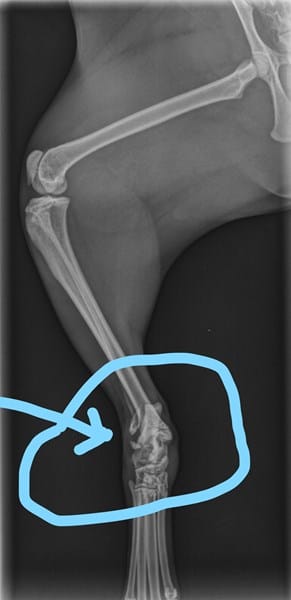

Esta es la radiografia de la pata derecha de mi gata. Solo se aprecia un pequeño huesito que se ve suelto. En la consulta nocturna que la lleve de emergencia solo le mandaron medicamentos pero ni la vendaron ni la enyesaron ni nada. Lo cual me deja la duda de si es una fractura o un esguince y si fue una mala praxis del veterinario en no inmobilizarle la pata para que sanara mejor